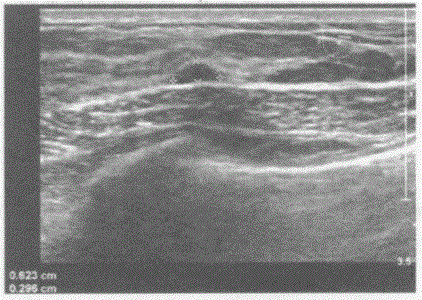

问题 临床资料:女,28岁,自诉双侧乳房胀痛。 超声综合描述:右乳腺腺体层厚1.1cm,左乳腺腺体层厚1.0cm,双乳腺腺体层结构紊乱,内可见大小不等管状无回声,右乳腺外下象限可见0.4cm×0.5cm低回声,右乳腺内上象限可见0.6cm×0.3cm低回声,边界清晰,形态规则。 超声提示:

选项 A.乳腺增生乳腺纤维腺瘤 B.乳腺增生病乳腺癌 C.乳腺增生病(囊实性) D.乳腺囊肿

答案 C